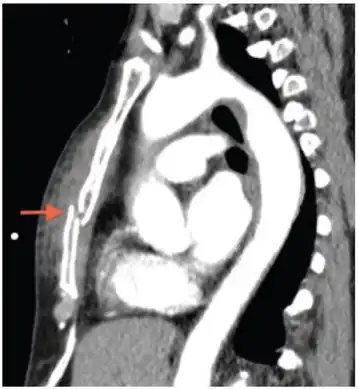

Computed tomography identifying displaced sternal fracture. -

CT scan showing a comminuted sternal fracture.[14]